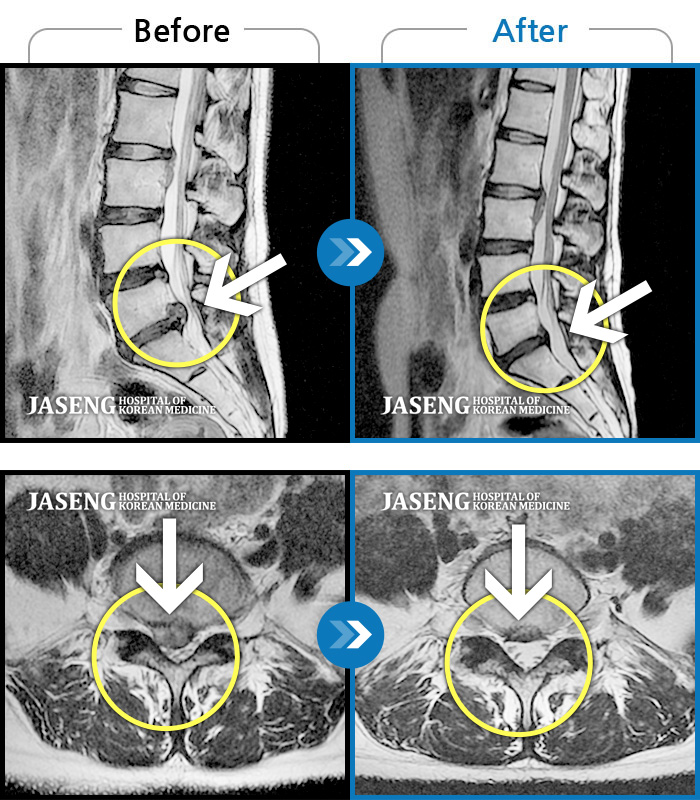

Before

After

환자에게 사전 동의를 받아 동일 조건에서 촬영되었습니다.

개인에 따라 치료 후 부작용이 발생할 수 있으니 의료진과 상담 후 치료를 진행하시기 바랍니다.

우측 허리 및 하지 전반적인 통증과 저린감

허리 통증 및 오른쪽 다리로 내려가는 심한 통증으로 혼자 보행 어려워 응급 내원